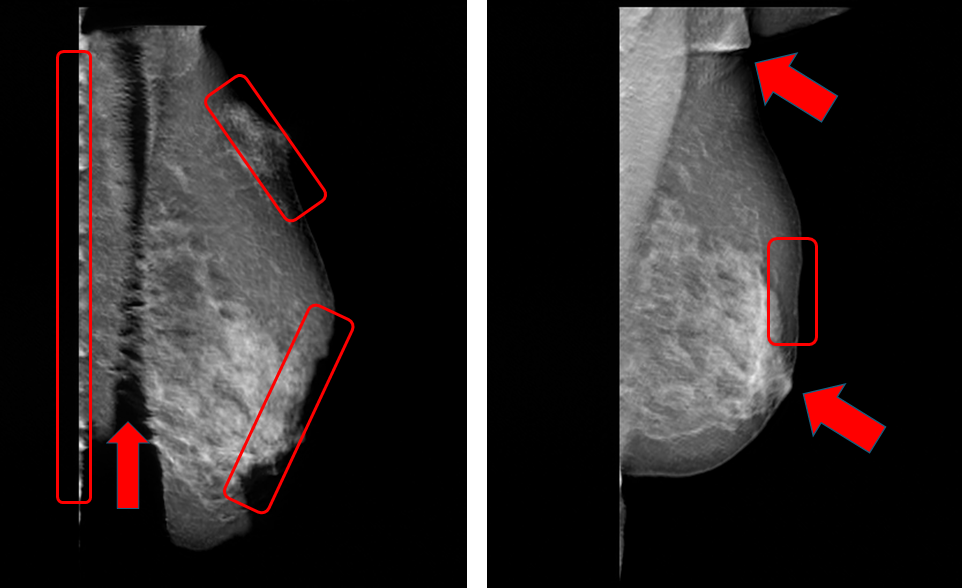

A key challenge with synthetic data obtained from generative AI models is the occurrence of unrealistic features or artifacts, which can arise when models prioritize matching overall data distributions over preserving fine-grained, image-level details or adherence to clinical or anatomical constraints. Figure 2 shows examples of synthetic mammography images from datasets created by training different generative AI models on the CSAW-M (Pinaya2023-kd) and VinDr-Mammo (pham2022vindr) patient datasets respectively. The red annotations in these images highlight various AI-generated artifacts, including unnatural geometric patterns, synthetic noise within breast tissue, and artificial discontinuities along tissue boundaries. These artifacts demonstrate failure modes where the generative AI model inadequately capture the natural anatomical shapes and morphological structures in real patient mammography, potentially introducing systematic biases that could compromise the diagnostic accuracy and clinical reliability of downstream AI models trained for lesion detection and classification tasks.

Figure 8 and Figure 9 present examples of hand-selected images from each partition as ranked by the proposed method for CSAW-syn and VMLO-syn, respectively. As shown in the figures, images in P1 () have visible shape artifacts. In P2 (1%-10%), CSAW-syn shows clear artifacts, while VMLO-syn exhibits minor distortions. In P3 (10%-100%), both datasets display well-formed breast shape without visible artifacts.

The figures also highlight that each synthetic dataset exhibits different types of artifacts. In CSAW-syn, artifacts are primarily local, such as multiple nipples, poorly formed nipple regions, and sharp chest wall angles. In contrast, VMLO-syn shows more global artifacts, with visibly malformed breast shape (below the 1st percentile in Figure 9), alongside minor local artifacts (1st-10th percentile) like non-smooth or angular boundaries.